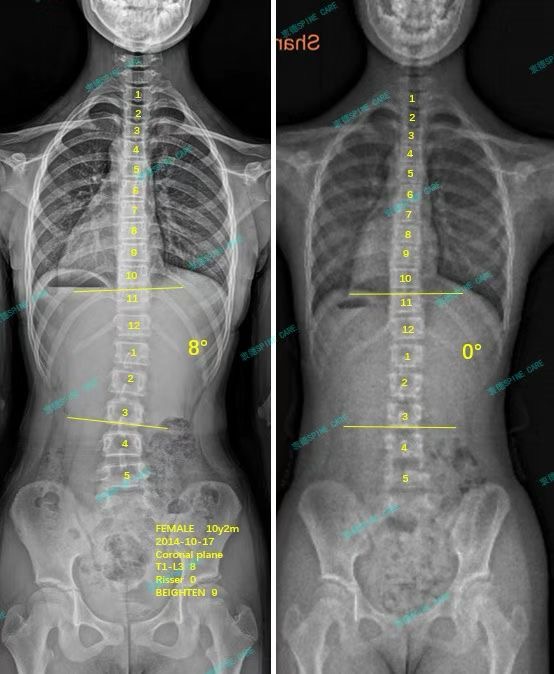

案例主人:叶子 发现侧弯年龄:10岁 侧弯情况:Cobb角度8度

大家好,我是叶子。那天在学校做脊柱侧弯检查,医生说我可能有脊柱侧弯,爸妈立即带我去拍x片,记得刚拿到检查结果的时候,发现我脊柱弯了8度,还有5度的旋转,我跟爸妈都吓了一跳,生怕它越来越严重,爸妈急得像热锅上的蚂蚁,到处打听哪里能治疗。后来在网上找到了衷德脊柱侧弯矫正与研究中心,这里的康复案例和矫正效果都很不错。

我在这里训练了三个月,右侧胸腰弯的角度从8度降到了0度,虽然还有旋转,但看起来整个人的体态好多了!真的很感谢衷德脊柱,不仅我的脊柱角度恢复得这么好,连我自己都觉得身体更轻松了,整个人精神多了。现在我走路都挺胸抬头的,同学们都说我看起来比以前更有气质了!